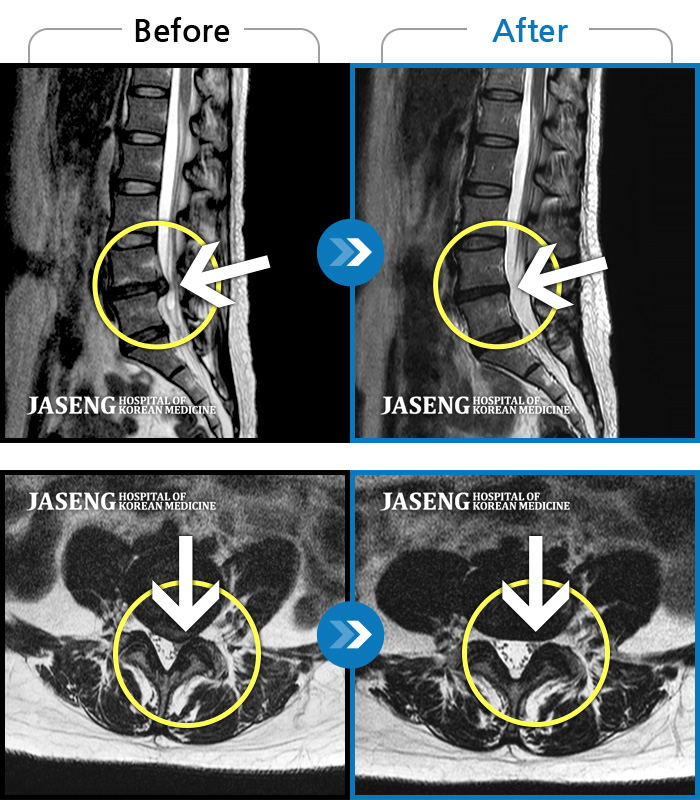

Before

After

환자에게 사전 동의를 받아 동일 조건에서 촬영되었습니다.

개인에 따라 치료 후 부작용이 발생할 수 있으니 의료진과 상담 후 치료를 진행하시기 바랍니다.

좌측 허리 통증으로 허리를 반듯이 펴고 서있기 힘들어 내원하셨습니다.

극심한 통증으로 허리를 조금도 움직이기 힘들었고, 오른쪽 허벅지 전면부 찌릿한 통증